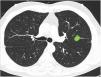

Clasificación de lesiones que sobrepasan líneas divisorias (fig. 2): en este bloque se valoró la uniformidad de criterio para clasificar una lesión como central (según una definición de centralidad (en los 2/3 internos) previamente establecida en el enunciado de la pregunta) en lesiones que sobrepasan las líneas divisorias, previamente trazadas en la imagen.

Figura 2.En este bloque se valoró la uniformidad de criterio para clasificar una lesión como central en lesiones que sobrepasan las líneas divisorias. Imagen 10: Considerando que la localización en los 2/3 internos del hemitórax corresponde con centralidad ¿Diría que el nódulo tiene localización? Central/Periférica. Imagen 11: Considerando que la localización en los 2/3 internos del hemitórax corresponde con centralidad ¿Diría que el nódulo tiene localización? Central/Periférica.

La mayoría de los participantes en la encuesta consideraron las lesiones según la mayor parte de su volumen se encontrase a un lado u otro de una línea divisoria previamente trazada en la imagen. Así pues, las lesiones predominantemente situadas en el lado periférico se catalogaron como periféricas (imagen 10) (92,8%) y las predominantemente situadas en el lado central, como centrales (imagen 11) (79,2%) sin apreciarse diferencias entre especialidades (tabla 2).

Categorización de lesiones que atraviesan líneas divisorias (con la mayor parte en la zona periférica Vs con la mayor parte en la zona central). La mayoría de los encuestados consideran que las lesiones se deben considerar según la mayor parte de su volumen se encuentre en un lugar u otro determinado. No se observan diferencias significativas entre grupos de especialidades diferentes ni para la primera pregunta ni para la segunda (aTest exacto de Fisher)